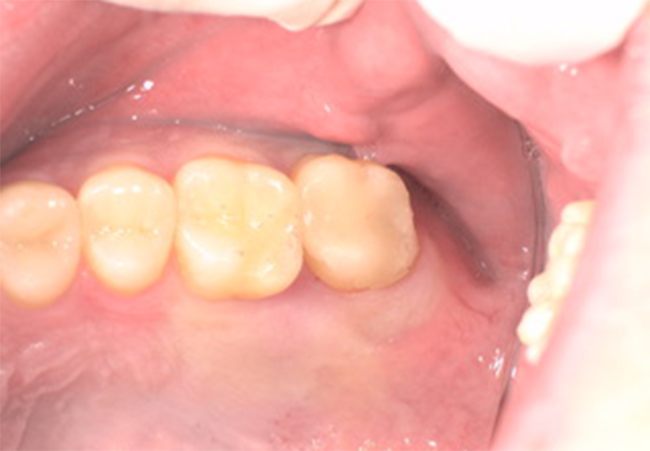

After②

年齢・性別

29歳男性

主訴

銀歯を換えたい

診査診断

審美障害

治療計画

セレックによるセラミック治療

治療期間・金額

1日2回 ¥33,000

リスク

知覚過敏、歯ぎしり等による破折